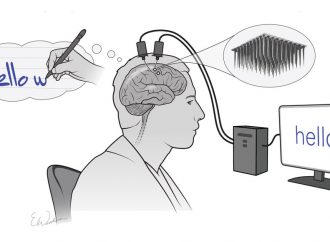

One burgeoning application is the use of AI in interpreting medical images – a field that relies on deep learning, a sophisticated form of machine learning in which a series of labelled images are fed into algorithms that pick out features within them and learn how to classify similar images. This approach has shown promise in diagnosis of diseases from cancers to eye conditions.